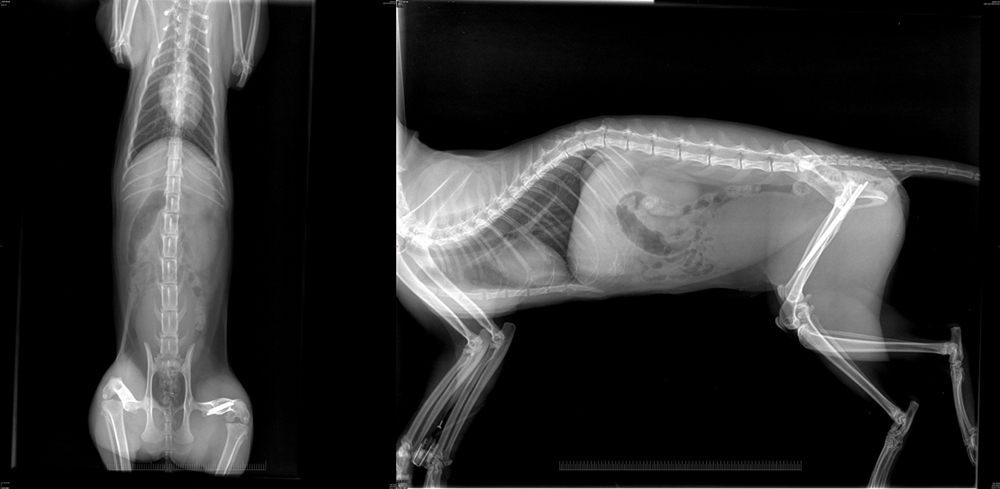

- 編號: 9506

主題: 墜樓金吉拉 申請者姓名: 鍾宜蓁 花色: 申請日期: 2020-02-03 18:38:31 申請者部落格: 申請者臉書網址: https://www.facebook.com/profile.php?id=100000314820889 所在縣市/合作醫院: 高雄市/弘恩動物醫院 治療費用: 12950元 需求人數: 30人 已結案 (2024-05-31 18:21:14) 報名人員: Cecilia Shih(已付款)、Oshale x6(已付款)、Haroro(已付款)、Peggy Lin x2(已付款)、小砡兒(已付款)、A&I(已付款)、陳昱先 x2(已付款)、Yt(已付款)、Jong Chia Liu(已付款)、becky jiang(已付款)、Layra(已付款)、lotto x2(已付款)、Anya Wu x2(已付款)、徐淳淳(已付款)、林燁(已付款)、祐子(已付款)、Doris Purple(已付款)、Jay Huang(已付款)、Mui x3(已付款)、 候補人員: 動物病情說明: 墜樓金吉拉是在左營區東門路117巷4號跟6號樓下被我先生發現的。發現的時候此貓已經癱倒在那裡。不確定是被丟下來還是自行跳下來的,無法分辨。我有張貼海報跟詢問附近居民,是否有人認識這隻貓,但並沒有人認識。因為本身有3個孩子要照顧一個7歲一個4歲一個1歲半。我每天要帶3個孩子在菜市場工作。經濟方面並沒有很穩定,也只是一般的小家庭。無法預知的醫藥費,讓我一度想放棄救援這隻貓咪,但是又捨不得看牠因為這樣而失去就醫的機會,所以在網路上詢問了網友,得知了貴協會很有愛心的在救援,懇請貴協會的幫忙。拜託貴協會能讓這隻貓得到醫助。謝謝 動物近況說明: 金吉拉目前狀況。可以自行吃東西。不用灌食。也會自行排尿排便。後腳神經部份。尚未恢復需做復建。所以目前在行走上還是無法很平穩的走路。謝謝。